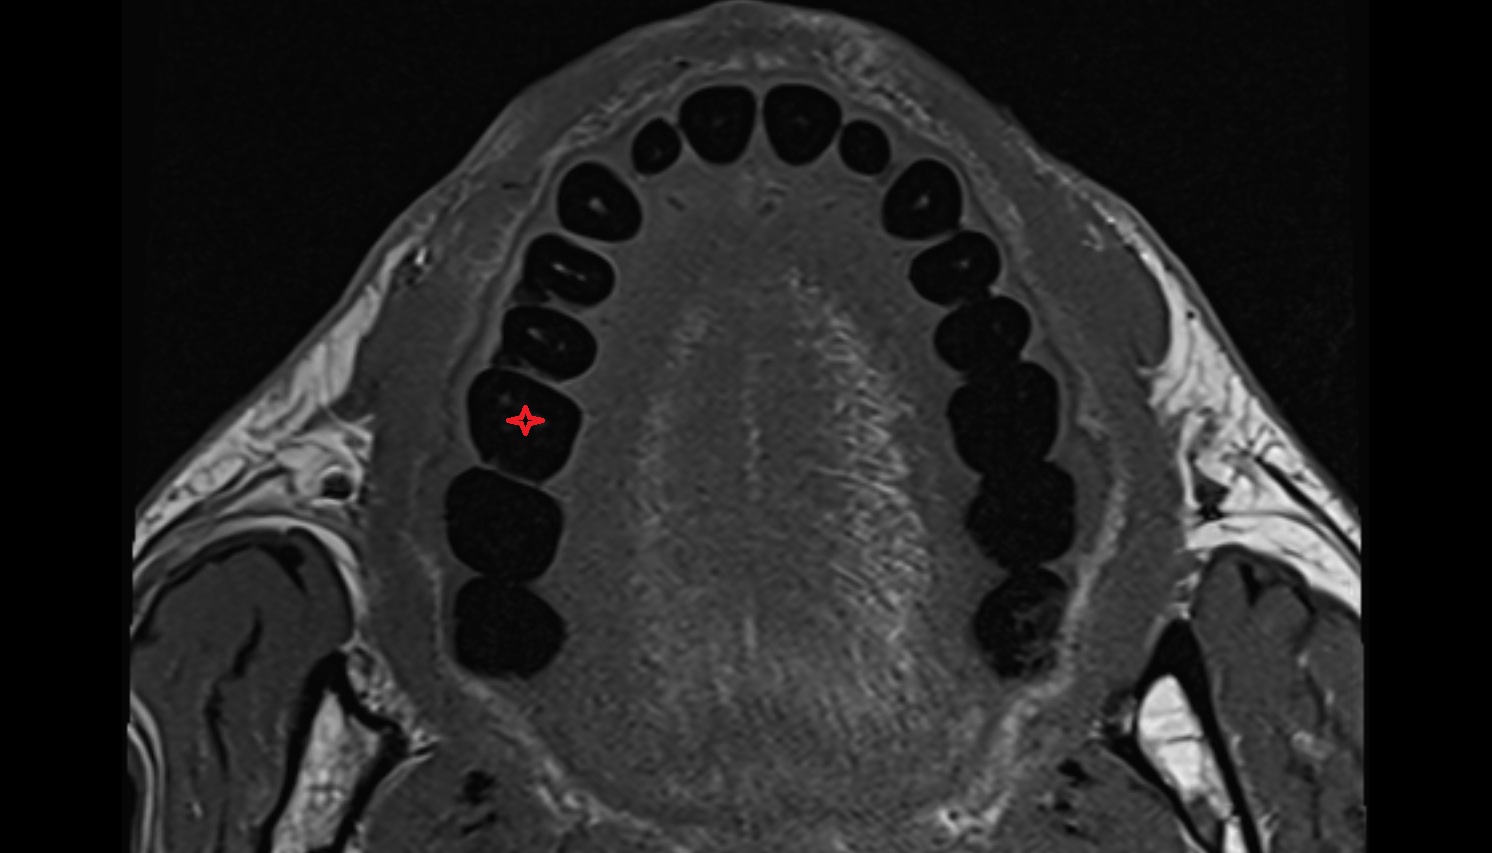

- Central inferior incisor tooth

- Central superior incisor tooth

- Inferior canine tooth

- Inferior cornu of thyroid cartilage

- Inferior first premolar tooth

- Inferior second molar tooth

- Inferior second premolar tooth

- Inferior third molar tooth

- Lateral inferior incisor tooth

- Lateral superior incisor tooth

- superior canine tooth

- Superior first molar tooth

- Superior first premolar tooth

- Superior second molar tooth

- Superior second premolar tooth

- Superior third molar tooth